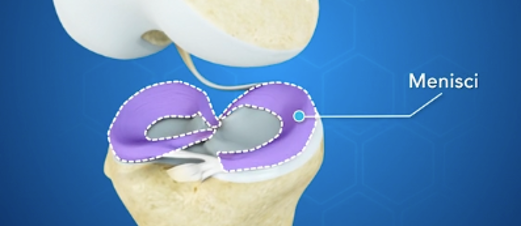

Meniszkuszok (gyűrűporc):

Minden térd ízületben két meniszkusz helyezkedik el. A belső (mediális) és a külső (laterális). A mediális meniszkusz vékony C-alakú réteg rugalmas porc (fibrotikus porc), amely a sípcsont felszínén, annak peremén fekszik. A meniszkuszoknak nincs saját vérellátása, ezért ha sérülnek a meniszkuszok nem tudnak természetese úton gyógyulni, regenerálódni. A meniszkuszok lengéscsillapítóként is viselkednek és segítik a térd forgó mozgását, védik az ízületi felületet és segítik a szinóviális folyadék keringését.

Mint másodlagos stabilizátorok, az ép meniszkuszok hozzájárulnak a térd stabilizálásához, melyet azonban elsősorban a szalagok, inak és a térd körüli izmok biztosítanak.